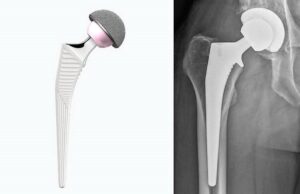

En los casos más graves de artrosis de cadera puede ser necesario recurrir a la cirugía. A día de hoy el tratamiento de elección es la prótesis de cadera que consigue aliviar el dolor y mejorar la función de la cadera.

Esta cirugía se suele realizar con anestesia general (completa) o anestesia raquídea (se duerme el cuerpo de cintura para abajo). La duración es alrededor de 60-90 minutos y mediante unos cortes precisos en el hueso se retira la articulación dañada y se colocan los implantes tanto en el fémur como en el acetábulo. Posteriormente se realizan pruebas de movilidad para ver que la prótesis recién implantada se mueve de manera adecuada y es estable. Una vez colocada la prótesis se cierra la herida quirúrgica.

Recuperación tras una prótesis de cadera

El ingreso medio es entre 2 y 5 días tras lo cual el paciente se puede ir a casa andando con unas muletas. Habitualmente los pacientes comienzan a notar mejoría del dolor inmediata, aunque como es lógico las primeras semanas existen las molestias habituales de una cirugía. El tiempo de recuperación para andar sin muletas es alrededor de 4-6 semanas, y la recuperación completa suele situarse alrededor de los 3 meses.